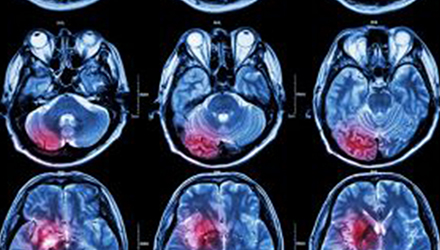

在這項(xiàng)研究中,研究人員使用功能核磁共振成像(fMRI)觀察大腦中血液含氧量的變化。研究人員首先研究了耳鳴患者和無耳鳴者的大腦活動,其目的是比較兩組受試者大腦處理情緒的方式。

在功能磁共振成像檢查中,受試者分別聽30種“愉悅”的聲音、30種“不愉快”的聲音和30種“中性”的聲音。這些聲音包括小孩咯咯笑,嬰兒啼哭,以及熱水壺?zé)_的聲音。

功能磁共振成像的結(jié)果顯示,當(dāng)暴露于情緒性聲音下,耳鳴患者大腦不同區(qū)域的活動比沒有耳鳴者的活動更強(qiáng)烈。接著,研究人員進(jìn)行了更深入的研究:耳鳴患者的大腦活躍性和耳鳴嚴(yán)重程度的關(guān)系。

調(diào)查結(jié)束后,再進(jìn)行功能核磁共振成像檢查。第二輪功能核磁共振成像顯示,那些耳鳴較輕的患者實(shí)際上使用了大腦不同的區(qū)域來處理情緒信息。

傳統(tǒng)觀點(diǎn)認(rèn)為,大腦中的扁桃體是處理情緒的關(guān)鍵,但此次研究發(fā)現(xiàn),那些不被耳鳴困擾的患者實(shí)際上使用更多大腦額葉來處理情緒。這類患者額葉活動更顯著的原因是,額葉通常更多地用于注意力、計劃和沖動的控制。